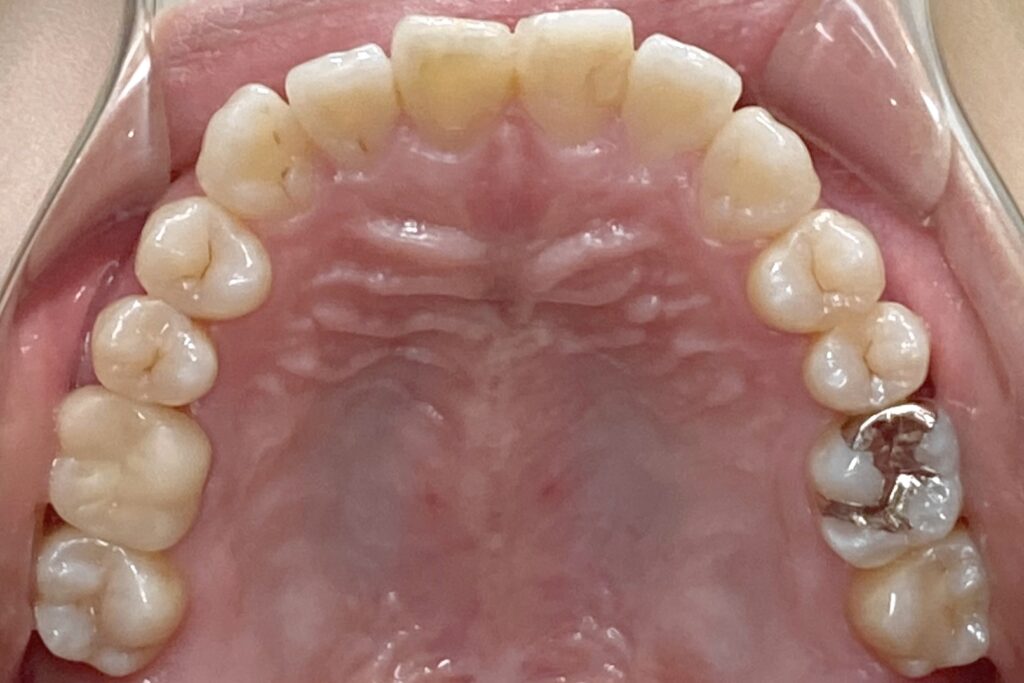

After